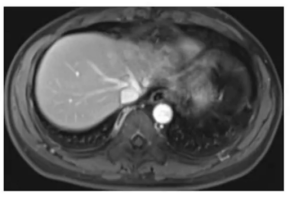

为明确IgG4相关性疾病的累及范围,进一步完善多部位影像学检查:

(1)上腹部增强核磁:提示肝左叶明显缩小,左肝静脉闭塞,考虑闭塞性静脉炎导致肝左叶废用性萎缩,肝右叶代偿性饱满。